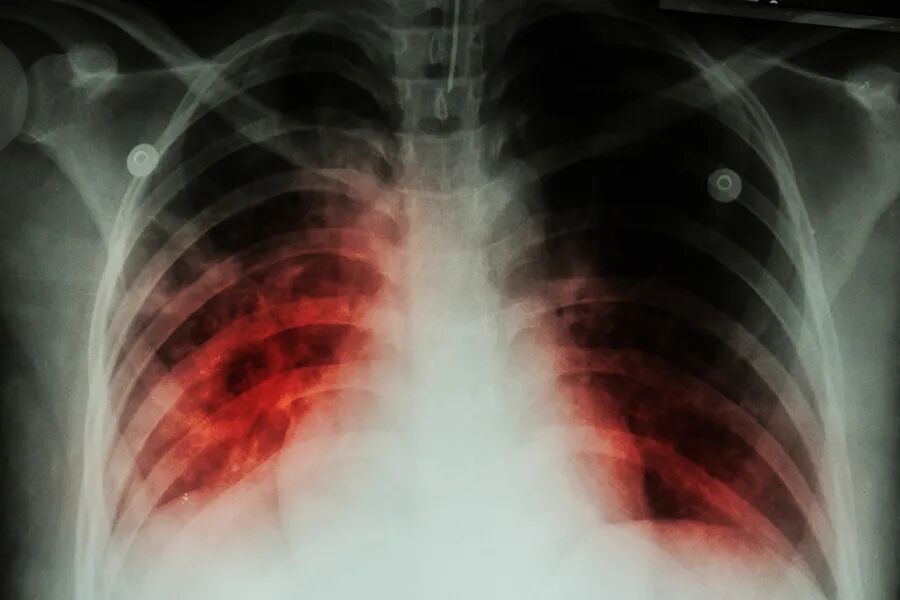

肺结核咯血一例

图片尺寸1598x1198